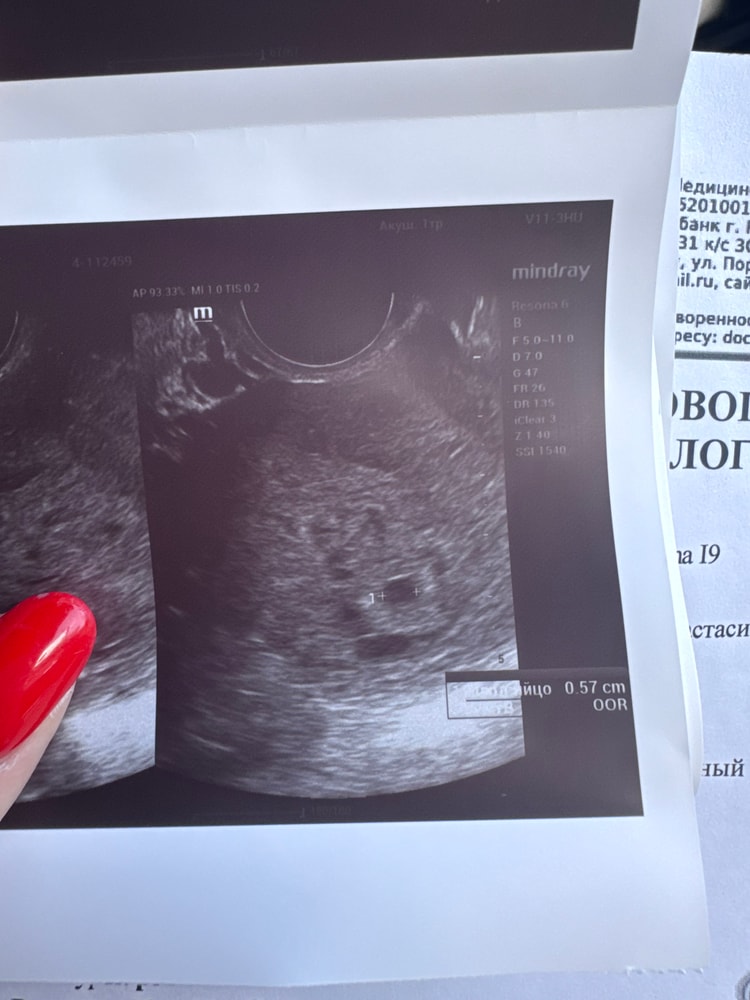

Маточная беременность, 1 плодное яйцо прикрепилось по задней стенке

размер 0,57 см ( 3 недели от зачатия)